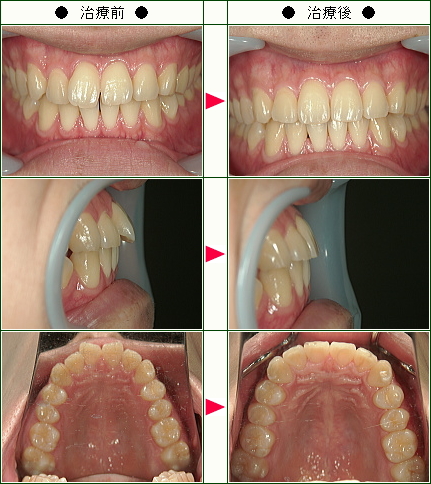

☆歯のデコボコ矯正症例(Y様 38歳 女性)